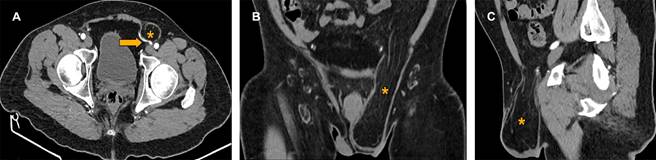

Se ingresaron un total de 292 pacientes, de los cuales, la mediana de edad fue 48.7 años (rango 36-60), del sexo masculino fueron 127 (43.5%) y del femenino 165 (56.5%). La media de IMC fue 29.6 ± 2.4. De acuerdo con la clasificación de IMC, los pacientes con sobrepeso fueron 166 (56.8%), con obesidad grado I, 93 (31.8%); obesidad grado II, 24 (8.2%) y obesidad grado III, 9 (3.1%). Confirmados de hernia inguinal (Figura 1) fueron un total de 117 (40.1%), de los cuales hernia inguinal indirecta (Figura 2) fueron 105 (36%) y directa fueron 12 (4.1%). La localización más frecuente fue izquierda 43 (14.7%), derecha 34 (11.6%), bilateral 40 (13.7%). El diagnóstico presuntivo habitualmente referido por lo cual se solicitó el estudio fue el dolor abdominal siendo 113 pacientes (38.7%) (Tabla 1).

Figura 2: Hernia inguinoescrotal indirecta. Tomografía computarizada con contraste intravenoso, con reconstrucciones en planos sagital y coronal de la región pélvica. A) Plano axial, se observa una hernia inguinal indirecta izquierda (*) al mostrarse los vasos epigástricos (→) mediales al saco herniario, que adopta una forma convexa que forma el “signo del gancho”. B) Plano coronal que muestra extensión del saco herniario hacia la región escrotal de lado izquierdo de contenido graso epiploico. C) Plano sagital.